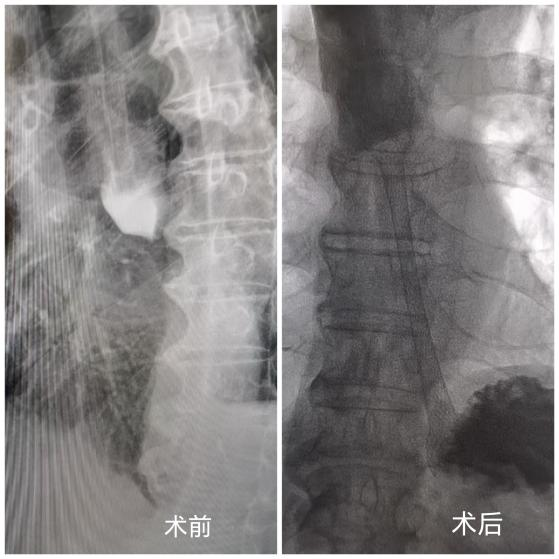

近日,黄石市第二医院成功为一名74岁食管癌患者实施食管球囊扩张术和支架植入术。术后仅三天,患者呕吐症状完全消失,恢复进食能力,生活质量得到显著改善。

针对胡老先生年事已高、身体耐受度弱的情况,黄石市第二医院介入放射科团队经过全面评估,决定采用食管球囊扩张联合支架植入术这一微创方案。手术无需开刀,经口腔引入微小导丝,将球囊精准送至食管狭窄部位,扩张后植入金属支架,快速撑开狭窄食管通道,恢复进食功能。“这类微创手术创伤小、恢复快,是高龄、体弱食管癌梗阻患者的理想选择。”介入放射科李青薛主任表示。